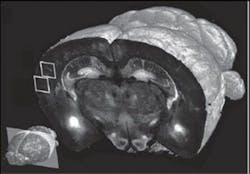

The technology can scan at resolution levels ranging from 1–2 μm to <1 μm; scans at the highest resolution level take about 24 hours, compared to one week using current methods, says associate professor Pavel Osten, who led the work. The team was able to produce full data sets, including final images, in 6.5 to 8.5 hours per brain, depending on the resolution. Each set of 260 coronal (top-to-bottom) slices was assembled by computer into 3-D renderings, which can be broadly manipulated to reveal hidden structures and features. At 10x magnification, the researchers were able to "visualize the distribution and morphology of green-fluorescent protein-labeled neurons, including their dendrites and axons," Osten notes.